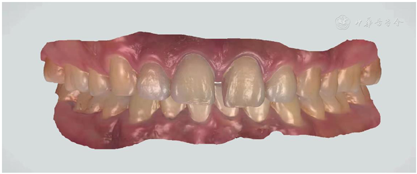

治疗计划为11、21贴面修复(邻面贴面)或正畸治疗。患者选择行贴面修复;龈上洁治,排龈,备牙前进行常规术前照相及比色(VITA2M2)。牙体预备:由11、21近中面扩展至唇近中线角,预备量约0.3 mm,基牙颈部预备与牙龈外形保持一致,肩台呈浅凹形,比色(VITA2M2)口扫;贴面试戴,邻接可,外形佳,与牙面边缘密合,色泽与天然牙匹配,患者满意同意粘接,粘结后检查正中颌、前伸颌及侧方颌,咬合无明显异常。见图3,图4,图5,图6,图7。

邻面贴面仅对牙齿的邻面部分进行牙体预备,最大限度的减少了对牙体组织的磨除量,满足了患者少磨牙的心理需求。同时,在其牙体预备过程中,越过唇舌面的线角的边缘线可以在重新塑形牙体外形的同时可以增加固位以及改善邻接。由于邻面贴面仅覆盖小部分牙面,所以修复体的颜色、质地和透光性都要应与天然牙相适应,以达到贴面与牙面在粘结区域自然过渡,以假乱真的程度,这也满足了患者对美学效果的需求。故对修复体的精度要求较高,要求术前拍摄记录和比色、粘接材料颜色的选择精确,同时制作过程中及时与技师的沟通交流,以达到较好的美学修复效果。